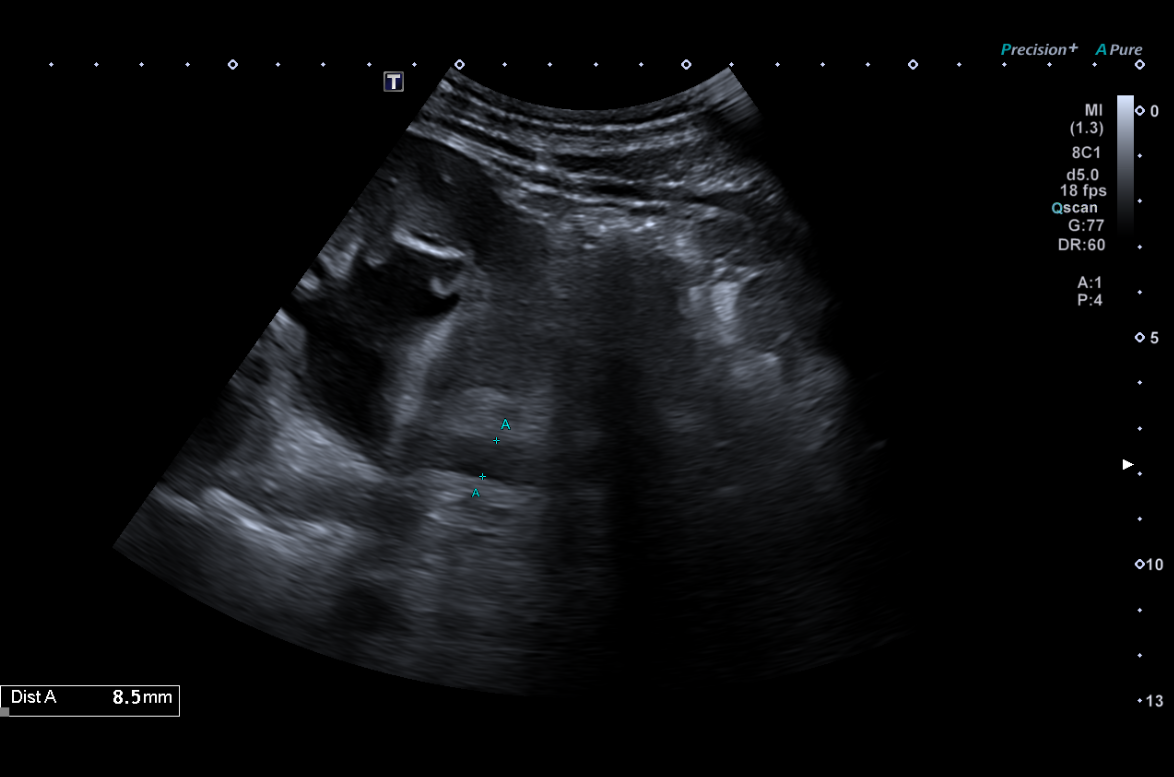

Se establece como hipótesis diagnóstica hidronefrosis. Se plantea como diagnóstico diferencial posible cistitis ulcerativa, así como uropatía obstructiva secundaria a consumo de ketamina. La ecografía clínica resulta determinante para la confirmación diagnóstica, evidenciando datos compatibles con obstrucción de la vía urinaria.

En vista del deterioro de la función renal del paciente, se decide ingreso hospitalario en medicina interna. Se realiza ecografía renal reglada por radiología la mañana siguiente, encontrando hidronefrosis grado III-IV bilateral.